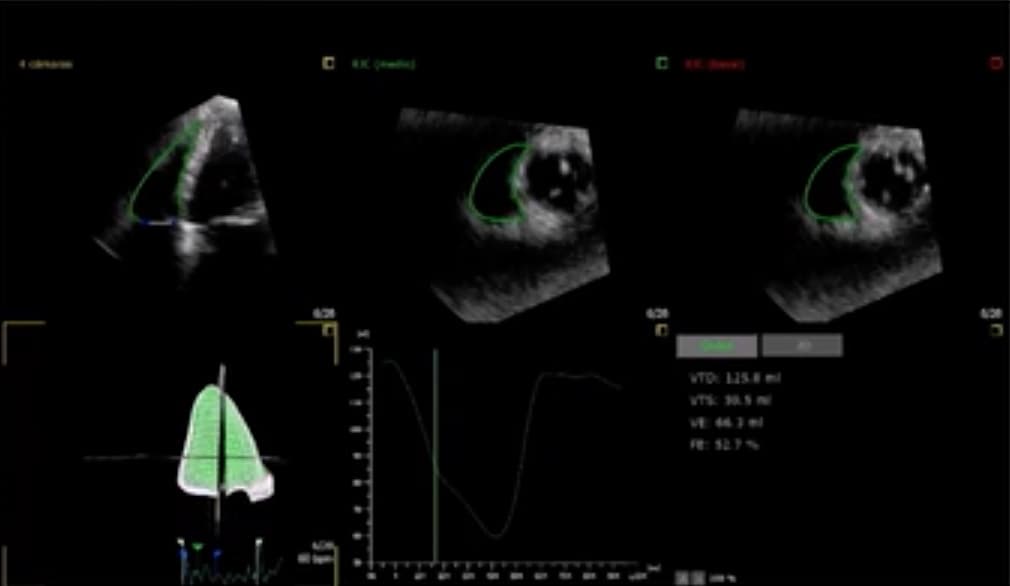

Le coroscanner est reconnu comme aussi sûr et moins coûteux que la coronarographie pour évaluer les douleurs thoraciques aigües. Une étude allemande publiée dans la Revue European Radiology évalue le rapport coût-utilité du coroscanner et confirme la meilleure rentabilité du coroscanner ainsi que so...